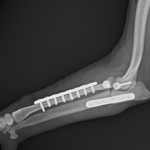

2歳の柴犬ちゃんが、生まれてすぐに痛めた肘に徐々に痛みが出てきたとのことで、主治医から診察と必要があれば手術をして欲しいと連絡がありました。CTでは橈骨頭が外側に脱臼して変位していました。また回転性の変形を伴っています。同時に尺骨にも湾曲が認められています。このような変形矯正には3Dプリンターで模擬手術を行いあらかじめシミュレーション手術をしておくと時間の短縮と正確な変形矯正が可能となります。このようなテクノロジーを動物医療にもどんどん取り入れていきたいと思います。また、骨きり部位にはPRFと自家海綿骨移植を行い治癒促進を期待します。